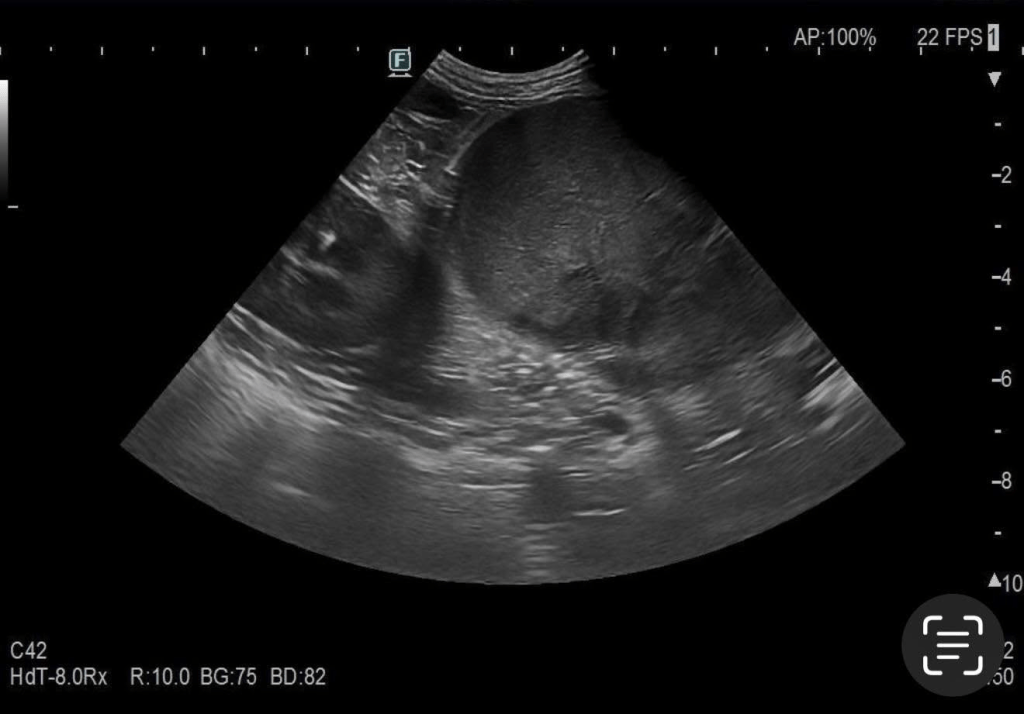

經過初步檢查,我們發現牠的肝膽指數異常升高,因此安排了超音波和X光影像檢查,影像結果顯示出牠的肝臟上有一顆明顯的腫塊。而在狗最常見的是肝細胞癌(HCC)。